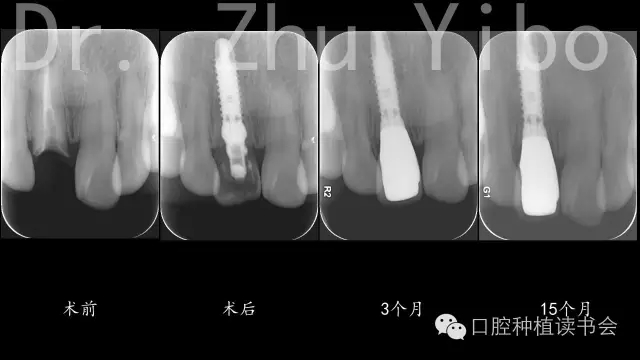

5、術(shù)后拍根尖片,確認臨時冠就位良好(圖12)。

640.webp (8).jpg

圖12

術(shù)前術(shù)后CBCT對比測量示:唇側(cè)牙槽骨穩(wěn)定(圖13)。術(shù)前術(shù)后石膏模型掃描,數(shù)字軟件重合對比測量:唇側(cè)牙齦組織穩(wěn)定(圖14)。

640.webp (15).jpg

圖13